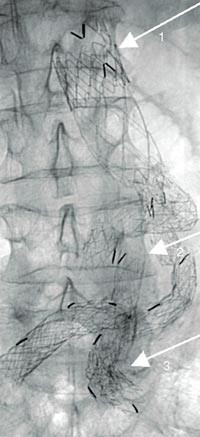

De komplikasjoner som knytter seg til behandlingen, kan inndeles i tidlige og sene. De tidlige knytter seg i stor grad til selve innsettelsen av protesen, hvor de anatomiske forhold er av vesentlig betydning. De sene komplikasjonene er forårsaket av stentgraftenes begrensede stabilitet, holdbarhet og aortasykdommens fortsatte utvikling med utvidelse av aneurismehalsen og bekkenarteriene, forskyvning av protesen når aneurismet skrumper eller at graftbeina glir opp i aneurismesekken (fig 2, 3). Dermed oppstår det lekkasje ut i aneurismesekken, som utsettes for systemtrykk på nytt. En del av disse komplikasjonene kan unngås med spesiallagede stentgrafter, suprarenal fiksering, embolisering av lumbalarterier, aa. iliacae internae samt god forankring i bekkenarterier. Med økt erfaring kan man også lettere skille ut de av aneurismene som ikke egner seg til stentgraftbehandling. De tidlige problemene er kjent og fører til hyppigere kontroller og behandling såfremt dette er indisert. Hos de pasienter hvor man finner at alt er i orden, tas kun årlige CT-kontroller. Lekkasje og ruptur kan oppstå når som helst imellom disse kontrollene (9, 10), noe som skjedde for to av våre pasienter.